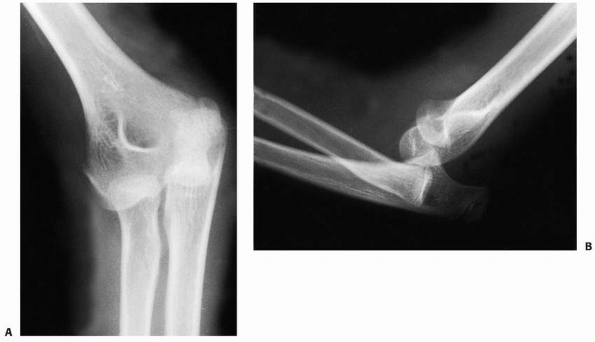

diagnostic of a posterior elbow dislocation. There is a greater

superimposition of the distal humerus on the proximal radius and ulna

in the anteroposterior view. The radial head may be proximally and

laterally displaced, or it may be directly behind the middistal

humerus, depending on whether the dislocation is posterolateral,

posterior, or posteromedial (Fig. 16-6). The

normal valgus angulation between the forearm and the arm usually is

increased. On the lateral view, the coronoid process lies posterior to

the condyles. The x-rays must be examined closely for associated

fractures. Subtle osteochondral fracture fragments can become entrapped

in the joint. If anatomic, congruent reduction is not feasible, and

further evaluation with computerized tomography or magnetic resonance

imaging is utilized to further define complex injury patterns.

FIGURE 16-6 Radiographic findings. A.

Anteroposterior radiograph. The radial head is superimposed behind the distal humerus. There is increased cubitus valgus. The medial epicondyle has not been avulsed. B. Lateral radiograph demonstrating that the proximal radius and ulna are both displaced posteriorly to the distal humerus. |